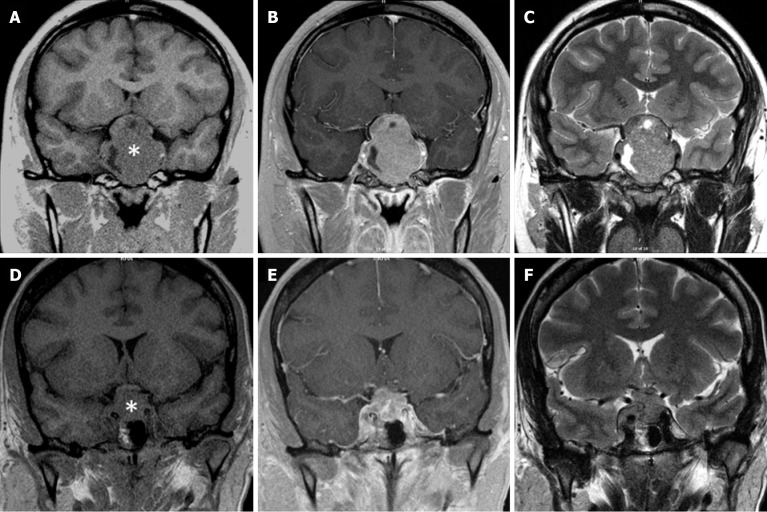

Primary sellar atypical teratoid/rhabdoid tumor (AT/RT) is the most aggressive sellar mass. Although rare, sellar AT/RT exhibits a very relentless clinical course and usually results in death within months to a few years after diagnosis. The best clinical evidence suggests that surgical debulking and timely adjuvant chemoradiation are most effective in prolonging survival. A preoperative radiological diagnosis of sellar AT/RT thus is crucial in informing patients and physicians about this devastating disease. This minireview summaries the imaging features of sellar AT/RT. magnetic resonance imaging features of sellar AT/RT and the much more common sellar mass, pituitary macroadenoma, are similar in most aspects: They are both isointense to brain gray matter on T1 and T2 imaging and enhance upon gadolinium administration. Suprasellar extension and cavernous sinus invasion are present in practically all cases of sellar AT/RT, but are also present in 50%-75% of pituitary macroadenomas, especially in large ones, suggesting that suprasellar extension and cavernous sinus invasion disproportionate to the tumor size may favor sellar AT/RT diagnosis. Since sellar AT/RT grows very rapidly and does not allow significant remodeling of perisellar structures, the imaging features of perisellar structures such as optic chiasm and cavernous sinus may be key for imaging diagnosis of sellar AT/RT although they have not been well described in sellar AT/RT. In limited cases of sellar AT/RT, optic chiasm degeneration and thinning, which are very common in pituitary macroadenoma, are not present, giving hope for using features of perisellar structures to diagnose sellar AT/RT by imaging.